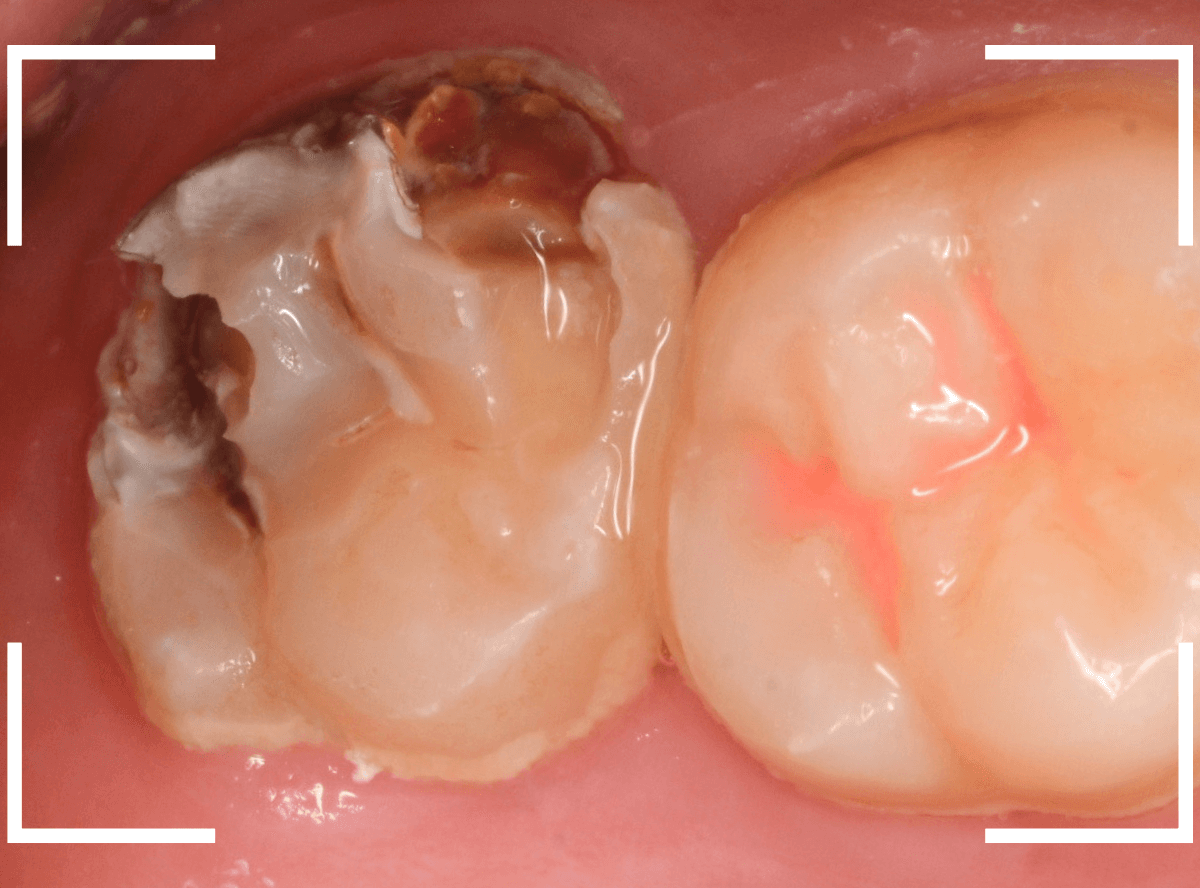

Case.11 外れたつめものの中は、ひどい虫歯

「上の奥歯のつめものが外れた」という訴えで来院された患者さんの例です。

つめものの外れてしまったつめものの中が虫歯になっているのが見えます。

レントゲン写真で確認します。

赤いラインが虫歯、青いラインが歯の神経です。

現在、つめてあるレジンの中まで虫歯が大きく進行し、ほぼ神経まで達しているのがわかります。

虫歯の治療を開始します。

奥につめてあるレジンも除去して中を確認します。

さらに慎重に虫歯を除去します。

手前の歯まで虫歯が進行しているのがわかります。

全ての虫歯を除去したところです。

薄皮一枚、神経ギリギリのところで虫歯を食い止められました。

しばらくは、お薬をつめて経過観察が必要です。

今回、つめものが外れてしまったのは、つめものの中が虫歯になったせいだと考えられます。

今回は、つめものが外れたのが受診のきっかけになったのが不幸中の幸いでした。